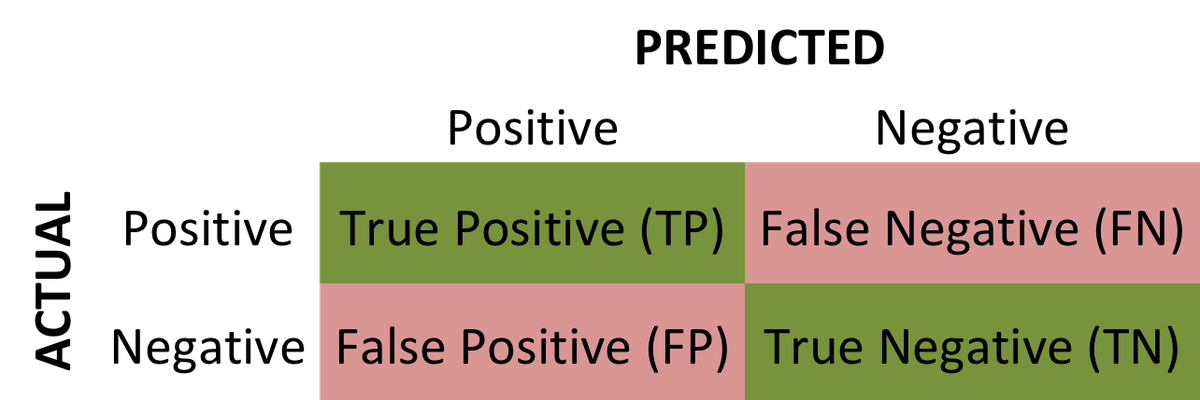

If the model successfully predicts the patients as positive, this case is called True Positive (TP) . If the model successfully predicts patients as negative, this is called True Negative (TN) . The binary classifier may misdiagnose some patients as well. If a diseased patient is classified as healthy by a negative test result, this error is called False Negative (FN) . Similarly, If a healthy patient is classified as diseased by a positive test result, this error is called False Positive(FP) .

We can evaluate a binary classifier based on the following parameters:

- True Positive (TP): The patient is diseased and the model predicts "diseased"

- False Positive (FP): The patient is healthy but the model predicts "diseased"

- True Negative (TN): The patient is healthy and the model predicts "healthy"

- False Negative (FN): The patient is diseased and the model predicts "healthy"

After obtaining these values, we can compute the accuracy score of the binary classifier as follows: $$ accuracy = \frac {TP + TN}{TP+FP+TN+FN} $$

The following is a confusion matrix , which represents the above parameters:

One commonly tool used for evaluating classification models is the confusion matrix. Let's explore what a confusion matrix is and how it's used for model evaluation:

In a binary classification problem (two classes, for example, "positive" and "negative"), a confusion matrix typically looks like this: